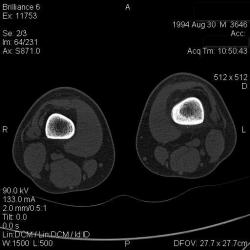

Мальчик 15 лет. Несколько месяцев назад начали беспокоить боли в коленных суставах. Травмы не было. Ребёнку был выставлен диагноз: болезнь Шлаттера, назначено лечение. На фоне лечения отмечалось значительное усиление болей, боли локализовались в левом коленном суставе. При дообследовании выявлена следующая рентгенологическая картина. Наши рентгенологи настаивают на срастающемся переломе. Но: 1) перелом без травмы? 2) бедро так не ломается

Да, на мой взгляд, состояние после обычного "травматического перелома" (трещина), не думаю, что имел место "патологический перелом", так как костная ткань "патологически изменена" минимально. "Перистальная реакция"локальная тоже есть, на КТ "локальная  зона склероза" - все это свидетельствует именно об этом. Хотя в памяти у меня хорошо отложился Ваш последний случай о локальном утолщении кортикального слоя, когда "яйца в гнезде" еще не было. То, что анамнестически "травмы не было" - ничего не значит. Вы, по всей видимости, тоже часто встречались с такими случаями, когда ребенок не акцентировал внимание на "травме", как таковой, хотя клиника есть, боль есть. Конечно, рентгенограммы - не дай бог - ни скиалогии, ни структуры.

В любом случае, мы посовещались и решили не рисковать. Завтра ребёнок идет на открытую биопсию.

Буквально заключение гистологов передать не могу (мой недочет, нужно было сразу выложить на сайтОй-ой-ой), но приблизительно помню - данных за специфический процесс нет, картина консолидирующегося перелома.

Так что, по всей видимости, это действительно был стресс-перелом. Который крайне редко встречается. Хоть статейку в журнал пишиУлыбаюсь.